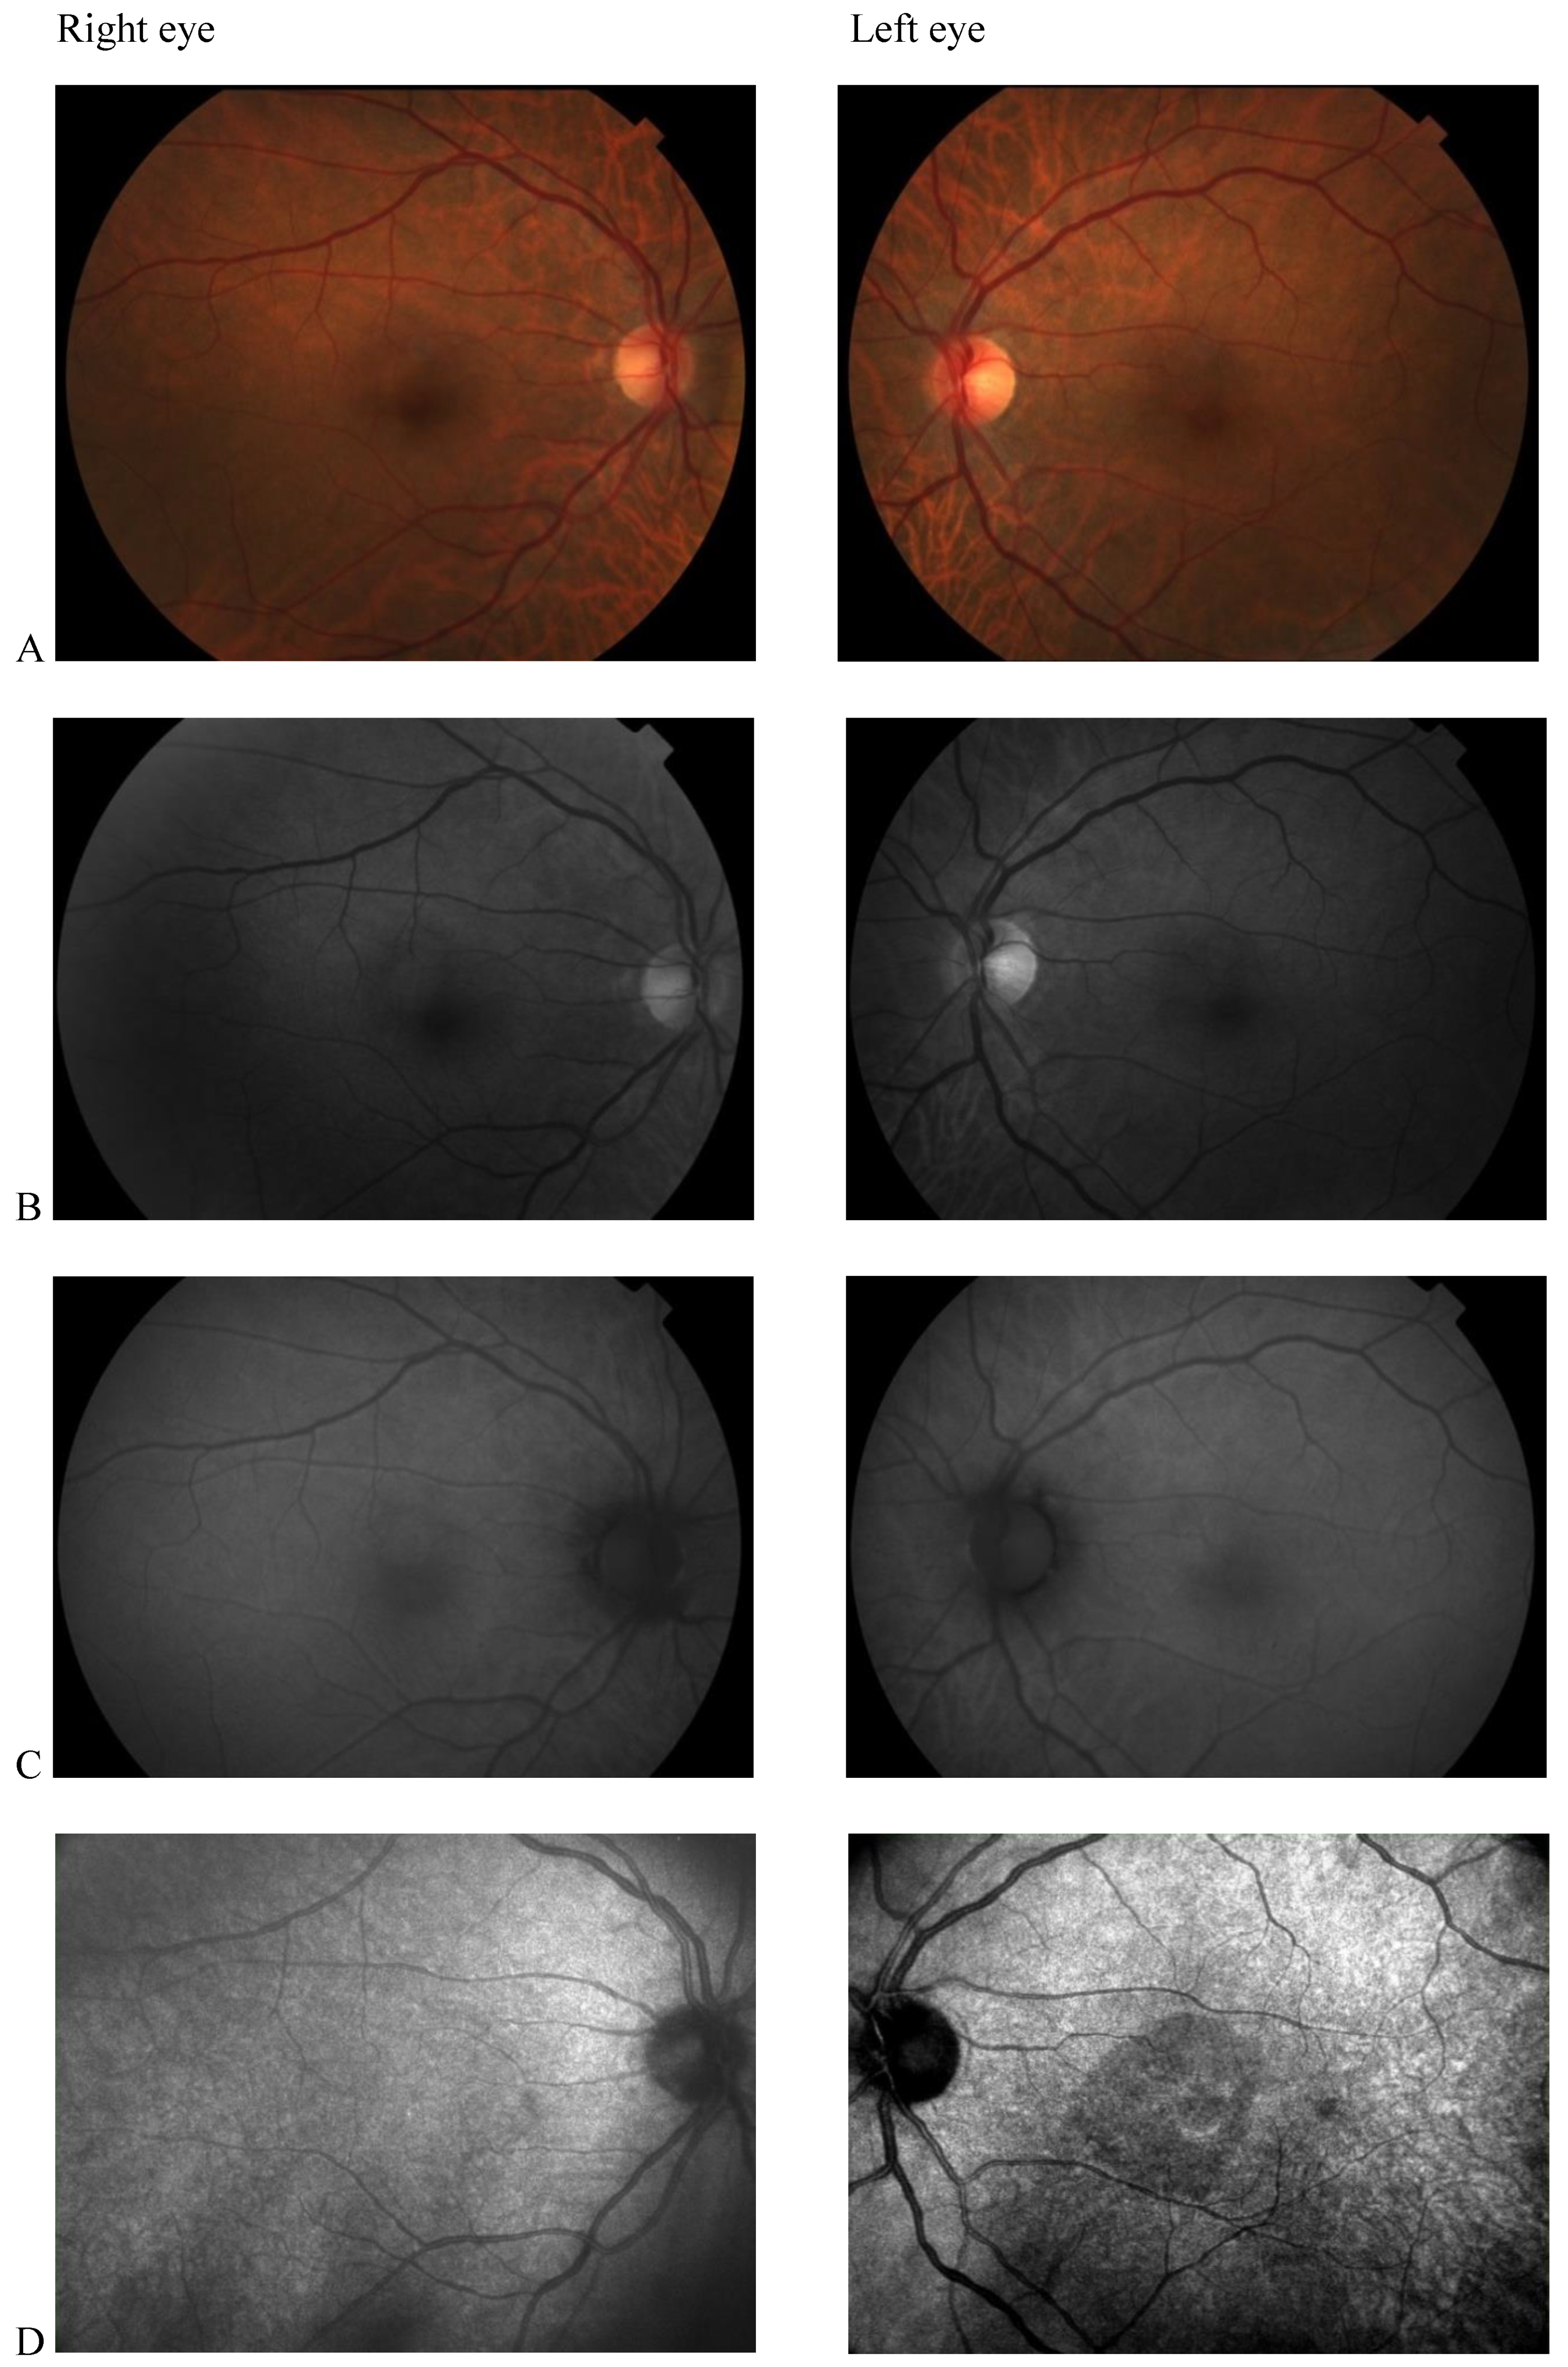

After six months of Tacrolimus suspension, the left eye BCVA improved to 20/25, and the central scotoma detected by 30.2 perimetry was reduced. The patient did not show up at the one-year follow-up visit. He came back to our Clinic 3 years later, showing a complete resolution of visual disturbances. BCVA was 20/20 in both eye eyes, and visual field testing with Humphrey perimeter demonstrated complete resolution of left eye central scotoma (Figure 3(1)). Despite the functional recovery, however, OCT scans did not show anatomical recovery. Central retinal thickness progressively reduced in both eyes (Figure 3(2)). In his right eye, retinal thickness reduction involved only perifoveal sectors of the OCT macular map and was not associated with any alterations in retinal layers morphology. In his left eye, retinal thickness reduction was greater and involved all sectors of the OCT macular map. Retinal layer segmentation revealed severe thinning of ONL that remained stable over time (Figure 3(3)).

Figure 3. (1) Humphrey visual field 30–2 map and total deviation map (A). baseline; (B) 6 months after Tacrolimus discontinuation; (C) 3 years after Tacrolimus discontinuation. Progressive resolution of the left eye central scotoma is evident; (2) Optical coherence tomography (OCT) Thickness Maps (A) baseline, (B) 6 months after Tacrolimus discontinuation, (C) 3 years after Tacrolimus discontinuation. Macular thickness progressively reduced in the left eye more than in the right eye; (3) OCT retinal segmentation analysis of both eyes (A) baseline, (B) 6 months after Tacrolimus discontinuation, (C) 3 years after Tacrolimus discontinuation. The retina layers are preserved in the right eye and thinning of the outer nuclear layer is evident in the left eye.